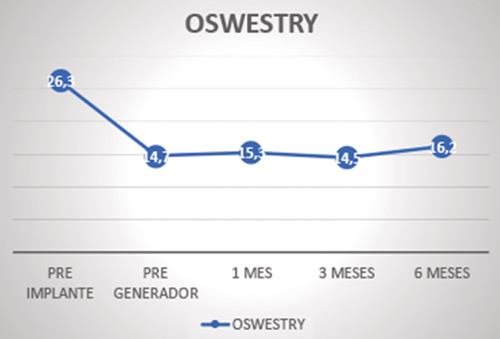

Los cambios en la funcionalidad según la escala Oswestry respecto a la situación basal (26 ± 9,6) fueron: 14,8 ± 10,2 (p = 0,001) a las 2 semanas, 15,4 ± 10,9 (p = 0,001) a 1 mes, 14,5 ± 11,2 (p = 0,002) a 3 meses y 16,3 ± 10,3 (p = 0,011) a 6 meses (Figura 3).

Fig. 3. Evolución del grado funcional según la escala Oswestry

En cuanto a la evolución del grado funcional, vemos cómo los resultados de la escala de Oswestry pasan de reflejar una incapacidad moderada (26,3) a una limitación leve (16,2). En el estudio Accurate se constata una mejoría en la subescala de funcionalidad del Short-Form-36 de 27 puntos para la EGDR y de 19 para la ECP. En los estudios de Kallewaard, que reclutaron 23 pacientes, los cambios en la escala de Oswestry fueron de 43,8 a 17,5, manifestando una limitación inicial mucho mayor que en nuetra serie (19,20).